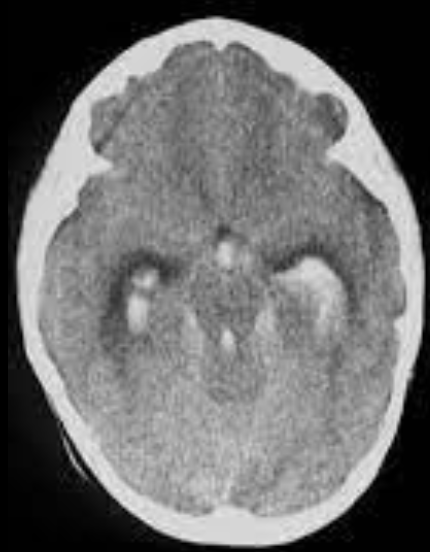

EVC hemorragico

Hipertensivo